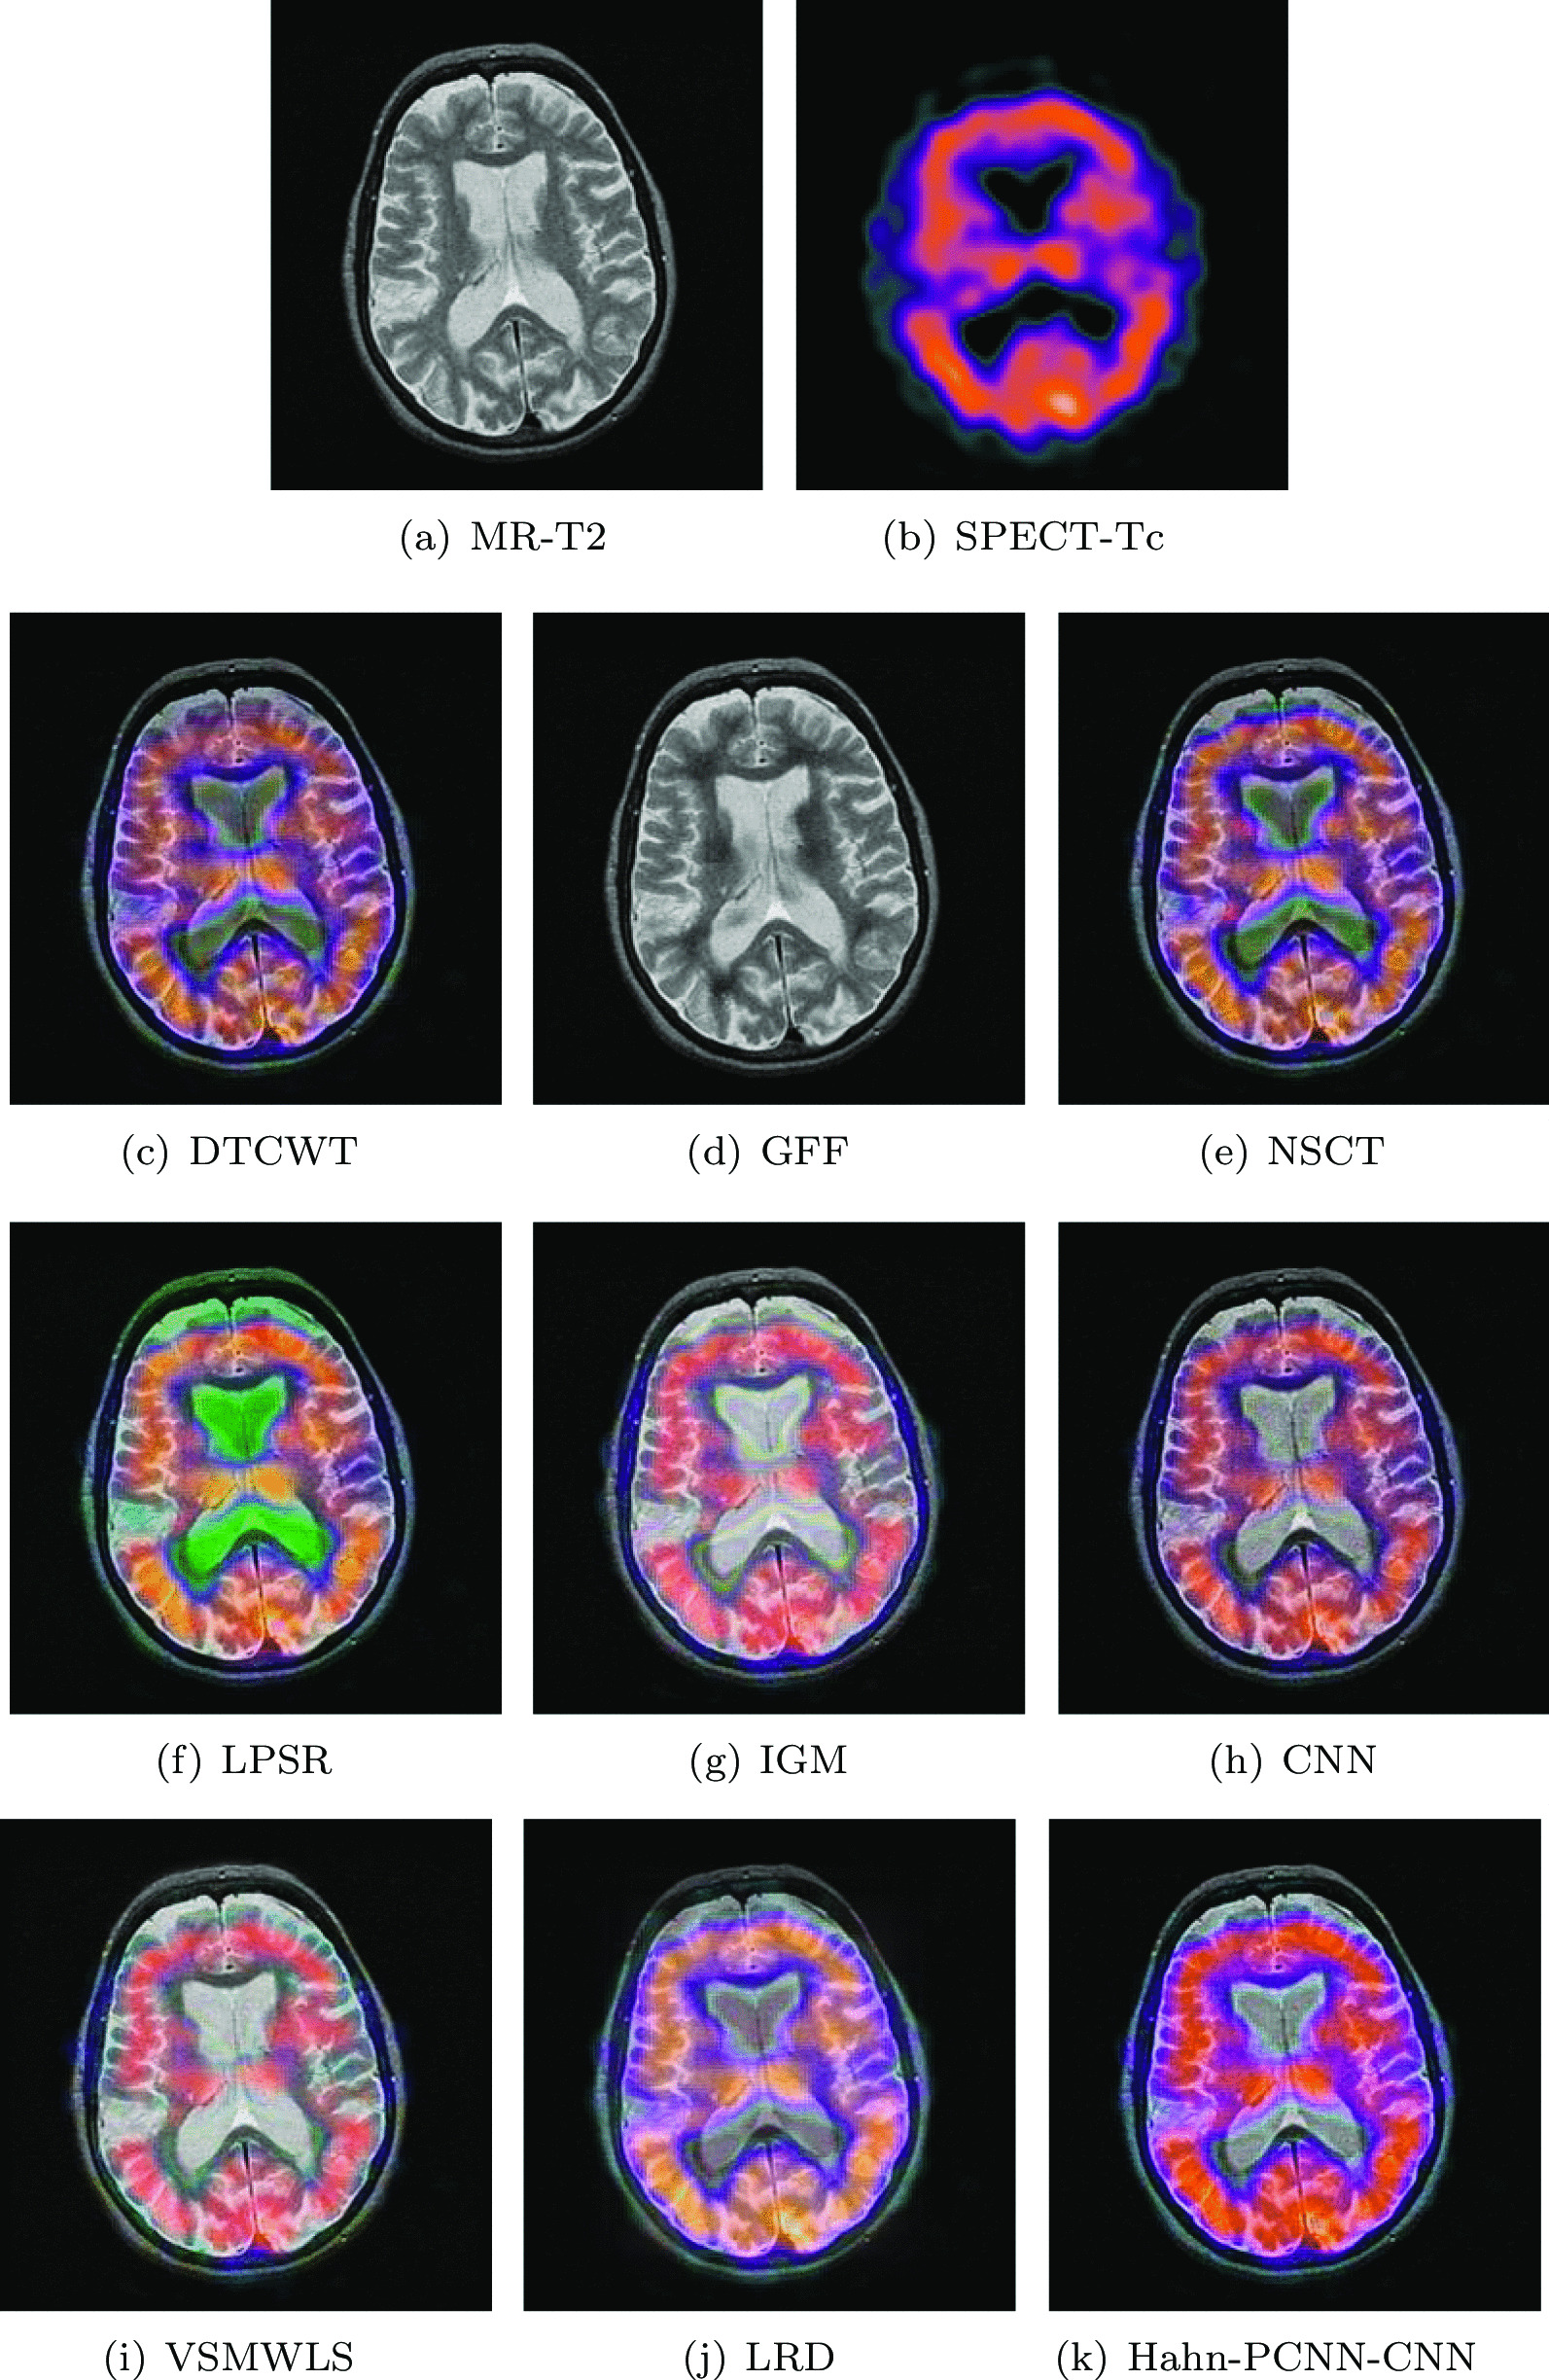

Huntington’s disease

The source images in Figs. 6 and 7 are from a 70-year-old woman who was clinically diagnosed as Huntington’s disease. In the MR-T2 image, the caudate nucleus has a tendency to shrink ; in the SPECT-Tc image, we can see the metabolism of the caudate nucleus in the shrinking process. Therefore, the fusion of the above two images has far-reaching significance. The structure information of the fusion image obtained by GFF, IGM and VSMWLS algorithms is well preserved, but the metabolism can hardly be expressed; the color information of the fusion image obtained based on the LPSR algorithm is seriously distorted; the fusion image obtained based on the LRD algorithm contains the source image. However, the detail information is seriously lost; the fused image obtained by DTCWT and NSCT algorithms can also obtain the source image information, however, the visual fidelity is somewhat poor and the low contrast leads to dark shadows in the caudate body; the fused image obtained by the GFF algorithm has a deviation in the expression of metabolic information at the edge of the caudate nucleus; our model performs well in retaining overall structural information and the expression of metabolic conditions in and around the caudate nucleus. The evaluation results shown in Tables 5 and 6 can prove that our model performs far better than other algorithms on the metric of structural similarity; on other metrics, the model is also quite satisfactory and stable.

Fig. 6.

The first set of fused MRI-SPECT images from 9 methods on huntington’s disease

Fig. 7.

The second set of fused MRI-SPECT images from 9 methods on huntington’s disease